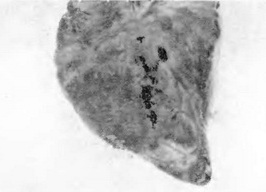

Печінка різко збільшена, в'яла, ламка, має глинистий колір, мускатний малюнок. Під серозною оболонкою різної величини крововиливу. На розрізі паренхіма вивертається (рис. 8).